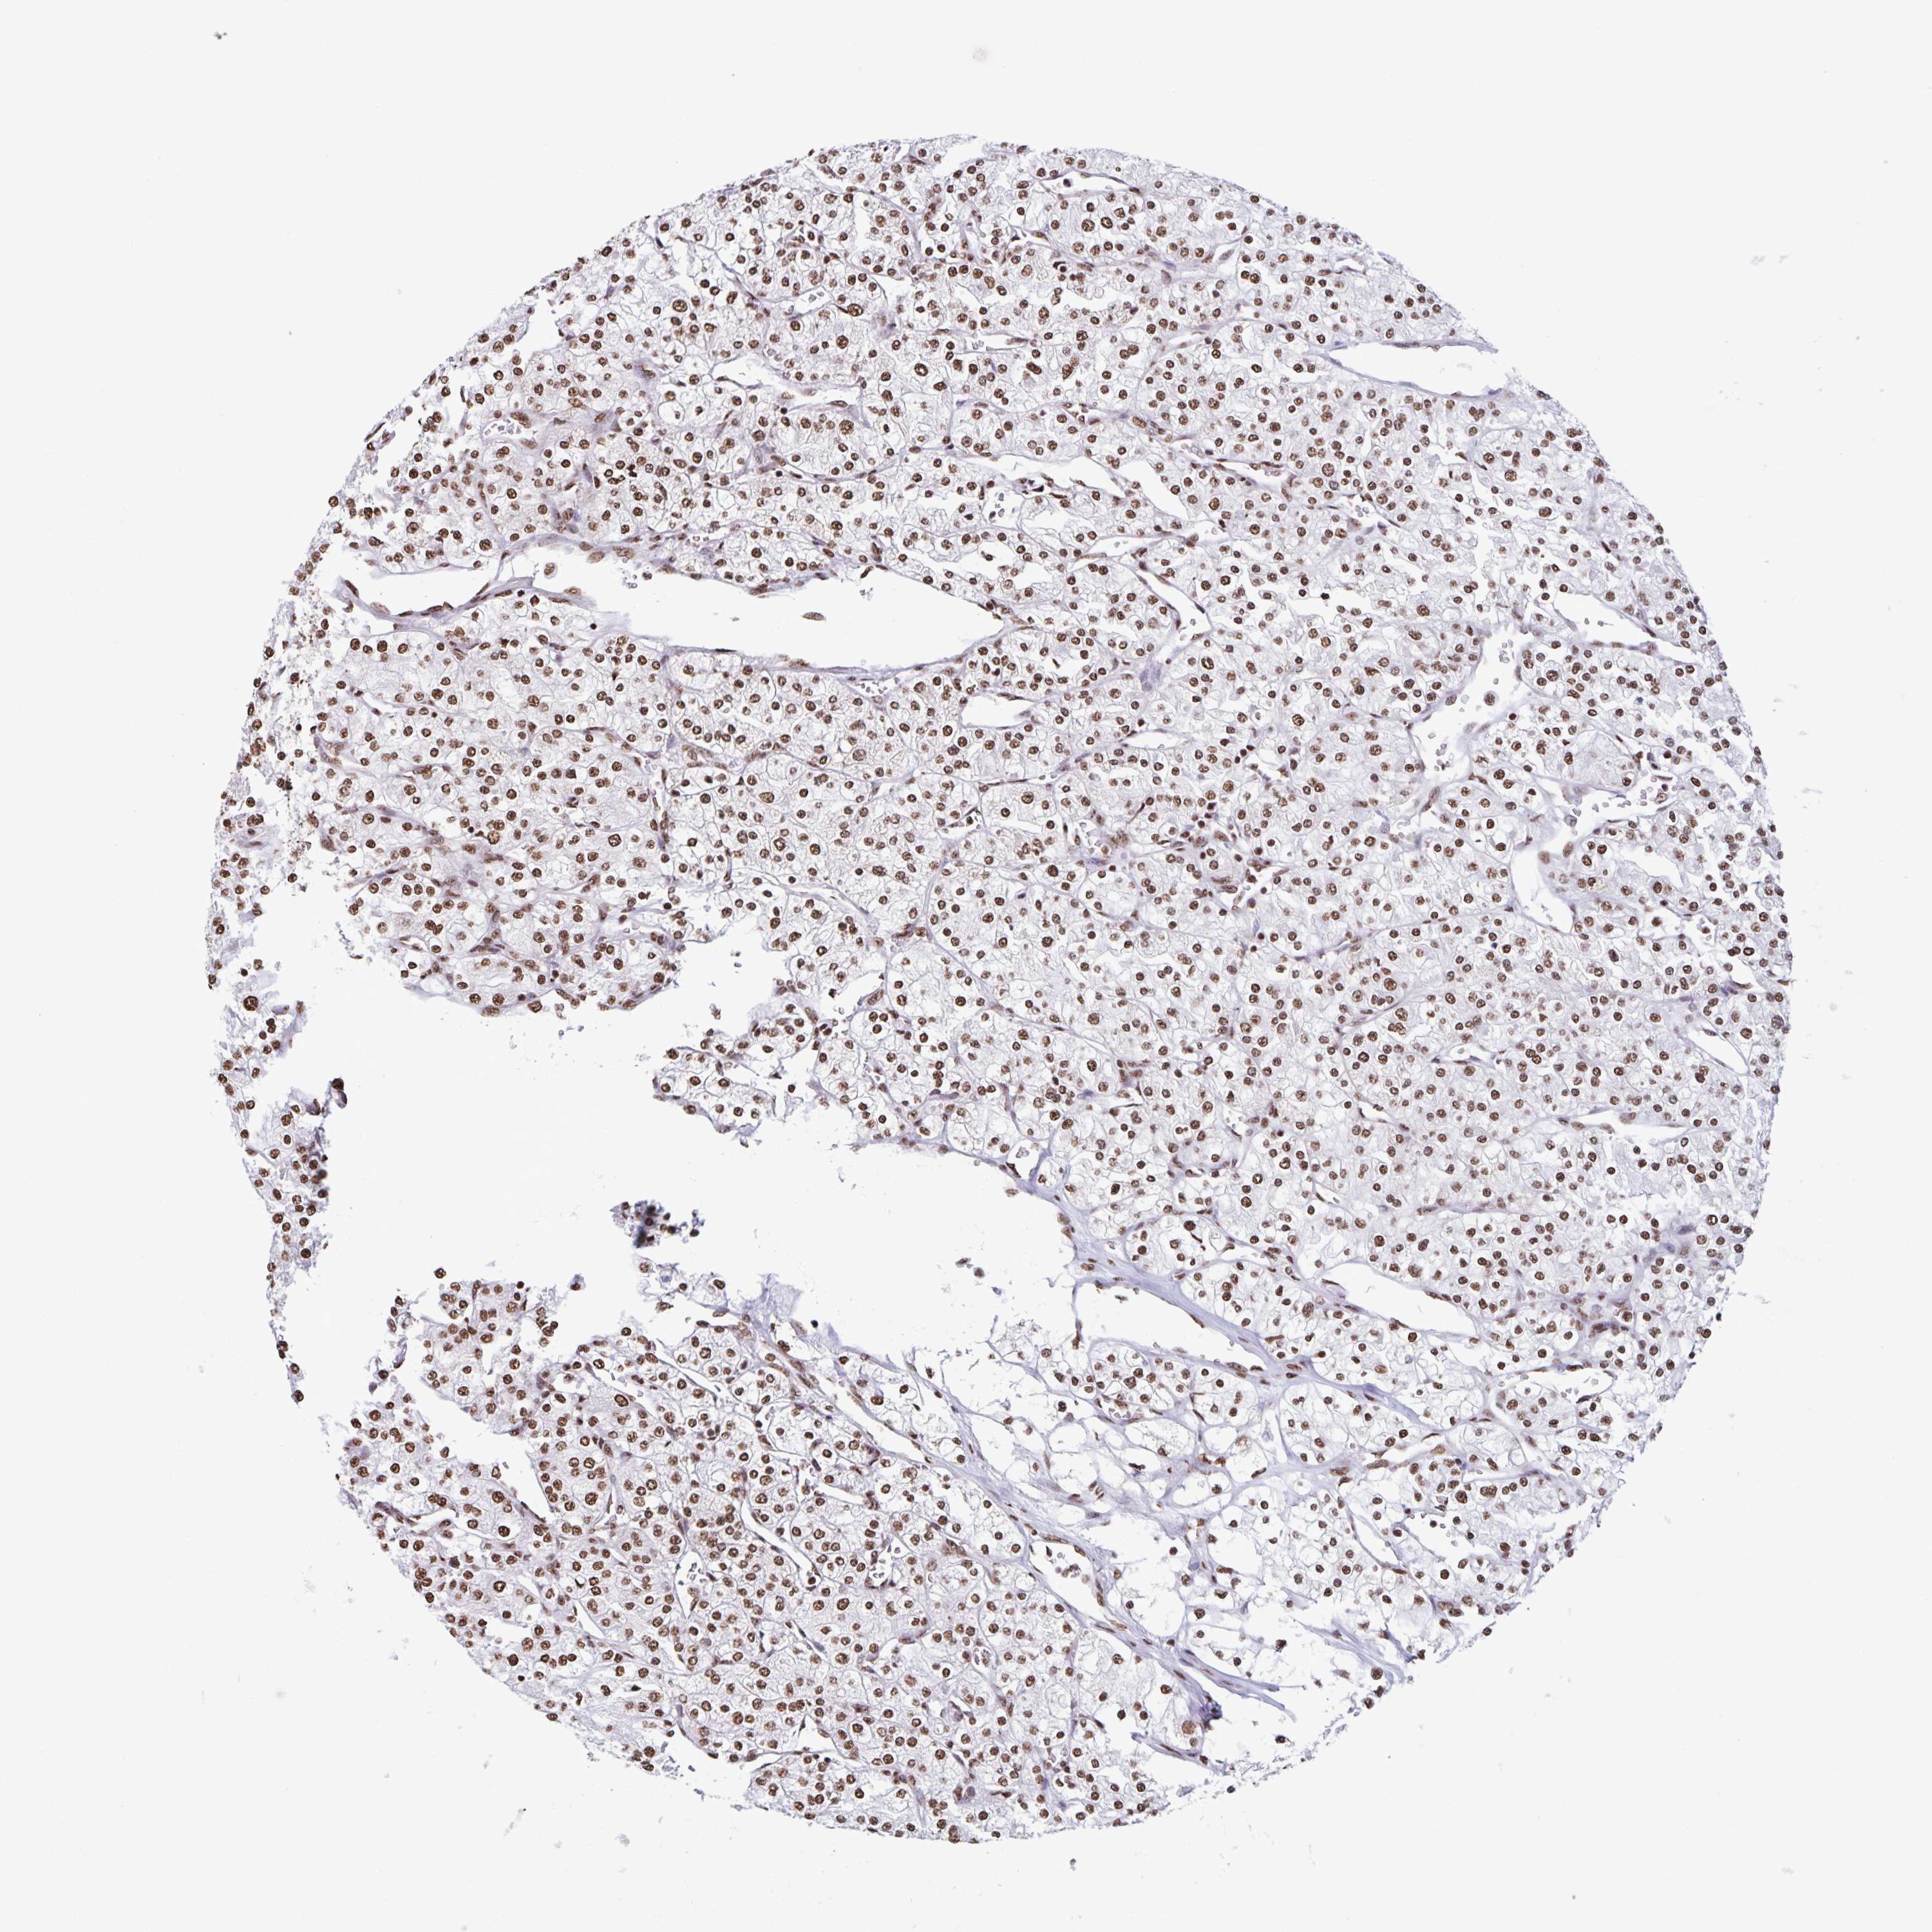

KIDNEY RENAL CLEAR CELL CARCINOMA (VALIDATION) - Interactive survival scatter ploti

The Survival Scatter plot shows the clinical status (i.e. dead or alive) for all individuals in the patient cohort, based on the same data that underlies the corresponding Kaplan-Meier plots. Patients that are alive at last time for follow-up are shown in blue and patients who have died during the study are shown in red.

The x-axis shows the expression levels (FPKM) of the investigated gene in the tumor tissue at the time of diagnosis. The y-axis shows the follow-up time after diagnosis (years). Both axes are complimented with kernel density curves demonstrating the data density over the axes. The top density plot shows the expression levels (FPKM) distribution among dead (red) and alive patients (blue). The right density plot shows the data density of the survived years of dead patients with high and low expression levels respectively, stratified using the cutoff indicated by the vertical dashed line through the Survival Scatter plot. This cutoff is automatically defined based on the FPKM cutoff that minimizes the p-score. The cutoff can be changed by dragging the vertical line or by entering a cutoff value in the square labeled "Current cut-off".

Under the Survival Scatter plot the p-score landscape (black curve; left axis) is shown together with dead median separation (red curve; right axis). Dead median separation is the difference in median mRNA expression between patients who have died with high and low expression, respectively. It is calculated as follows: median FPKM expression of dead patients with high expression - median FPKM expression of dead patients with low expression. This is intended to aid the user in visually exploring custom cutoffs and the associated p-scores and dead median separation.

Individual patient data is displayed and can be filtered by clicking on one or more of the category buttons on the top of the page. Categories describing expression level and patient information include: high, low, alive, dead, female, male and tumor stages. The scale of the x-axis can be toggled between linear and log-scale by clicking on the "x log" button. Mouse-over function shows TCGA ID, patient information and mRNA expression (FPKM) for each patient.

& Survival analysisi

Kaplan-Meier plots summarize results from analysis of correlation between mRNA expression level and patient survival. Patients were divided based on level of expression into one of the two groups "low" (under cut off) or "high" (over cut off). X-axis shows time for survival (years) and y-axis shows the probability of survival, where 1.0 corresponds to 100 percent.

DUT is not prognostic in Kidney Renal Clear Cell Carcinoma (validation)

Best expression cut offi

Based on the FPKM value of each gene, patients were classified into two groups and association between prognosis (survival) and gene expression (FPKM) was examined. The best expression cut-off refers the FPKM value that yields maximal difference with regard to survival between the two groups at the lowest log-rank P-value. Best expression cut-off was selected based on survival analysis .

When clicking on this number, the vertical dashed line indicating cut-off, the interactive survival plot, and the Kaplan-Meier curve will be adjusted to show results based on the best expression cut-off.

: 74.19

TCGA RNA samplesi

RNA-seq data is reported as average FPKM (number Fragments Per Kilobase of exon per Million reads), generated by the The Cancer Genome Atlas (TCGA) .

Normal distribution across the dataset is visualized with box plots, shown as median and 25th and 75th percentiles. Points are displayed as outliers if they are above or below 1.5 times the interquartile range. FPKM values of the individual samples are presented next to the box plot.

Average pTPM 78.7

Number of samples 100